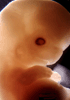

Carnegie Stage 20 (50 post-ovulatory days)

Most embryos at stage 20 are approximately 50-51 postovulatory days old and measure 21-23 mm in length. Distinguishing criteria for this stage include upper limbs slightly bent at the elbows, short stubby fingers, hands curving over the cardiac region but still far apart from each other, and a fringe-like vascular plexus that marks growth centers laterally in the superficial tissues of the head.

Although some of the photographs below show abnormal embryos, the animations and MRI slice images all depict normal embryos. Abnormal embryos are noted in the titles of the large photos when they are opened.